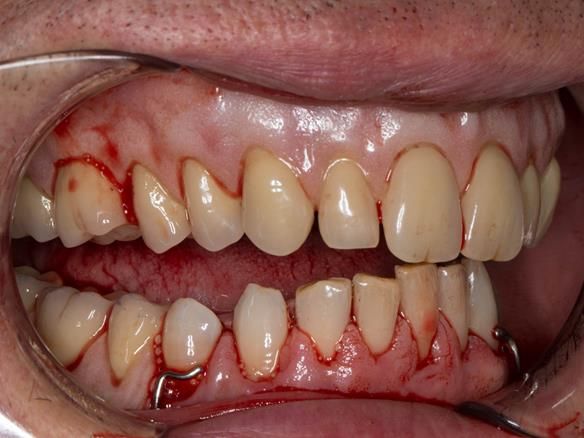

This 52 year old man was referred to me from his general dental practitioner in 2018.

10 years prior to consultation the patient's general dentist diagnosed periodontitis and referred him to Manchester Dental Hospital. He received a treatment plan to manage the periodontitis. Unfortunately, this was not acted on. Four years ago gaps developed between the upper front teeth. Orthodontic treatment was provided to align the teeth. A bonded retainer was fitted onto the upper front teeth. Approximately one year prior to consultation with me the patient noticed the teeth moving again. He consulted his orthodontist, who advised no further orthodontic treatment. One month prior to the consultation with me the upper left central incisor fell out whilst eating.

- Generalised periodontitis; stage IV grade C: currently unstable, risk factors: smoker.

- The remaining maxillary teeth had hopeless prognosis in the short term. They exhibited 80 - 100% alveolar bone loss with increased mobility (Grade 2 - 3).

- The lower right second premolar and lower left first premolar (LR5 LL4) had hopeless prognosis in the short term. They exhibited 80 - 100% alveolar bone loss with grade 3 mobility.

- The remaining mandibular teeth had approximately 30 - 50% alveolar bone loss with grade 1 mobility.

The clinical situation and treatment process is shown in detail below with photographs.